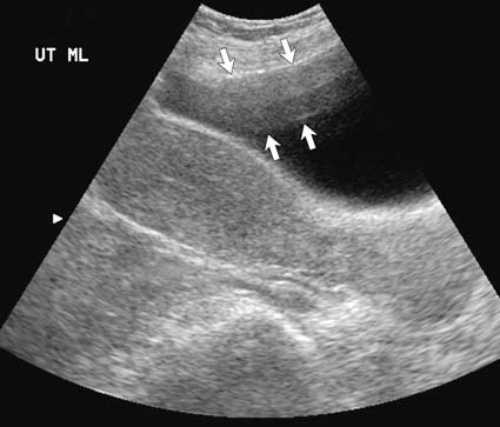

Рисунок 1. УЗИ мочевого пузыря. Стрелками указан участок реверберации в передних отделах мочевого пузыря

Реверберация обусловлена отражением ультразвука внутри тканей. Многократное отражение приводит к образованию дополнительного эха, которое интерпретируют как более глубокое, чем на самом деле. Идентифицируют артефакты реверберации по горизонтальным линейным эхо, которые располагаются на одинаковых промежутках с постепенно снижающейся интенсивностью.

Снизить выраженность артефакта реверберации можно с помощью гармонического изображения (например, реверберация при УЗИ печени в некоторых случаях может маскировать кисту или объемное образование).